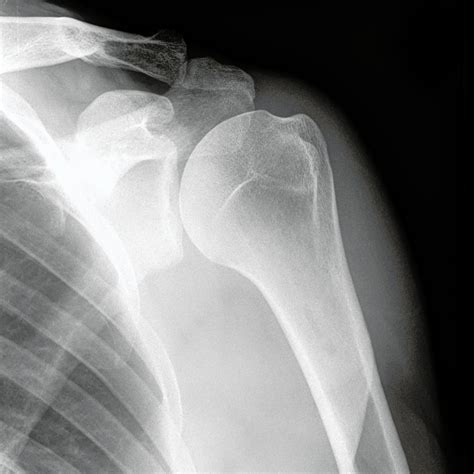

Shoulder flicking, crunching, clicking - bad? GX Physio